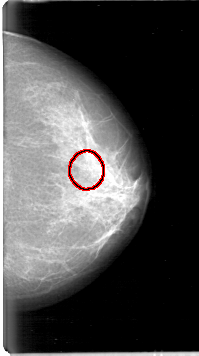

D_4054_1.LEFT_CC

LEFT_CC LINES 5326 PIXELS_PER_LINE 2971 BITS_PER_PIXEL 12 RESOLUTION 43.5 OVERLAY

FILE: D_4054_1.LEFT_CC.OVERLAY

TOTAL_ABNORMALITIES 1

ABNORMALITY 1

LESION_TYPE CALCIFICATION TYPE MILK_OF_CALCIUM DISTRIBUTION CLUSTERED

ASSESSMENT 0

SUBTLETY 3

PATHOLOGY BENIGN

TOTAL_OUTLINES 1